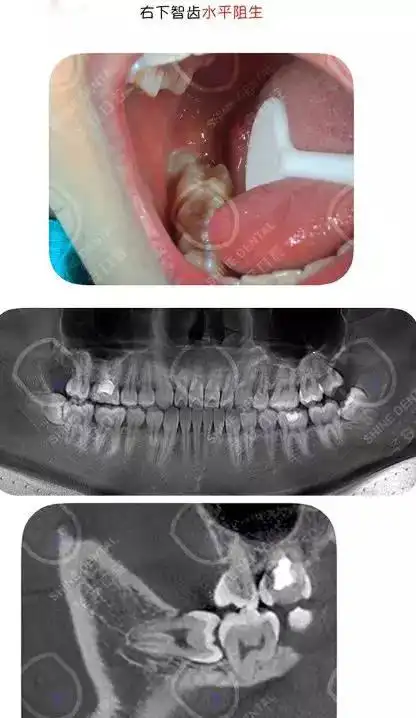

医生一定要让拔智齿的真相是什么?_手机搜狐网